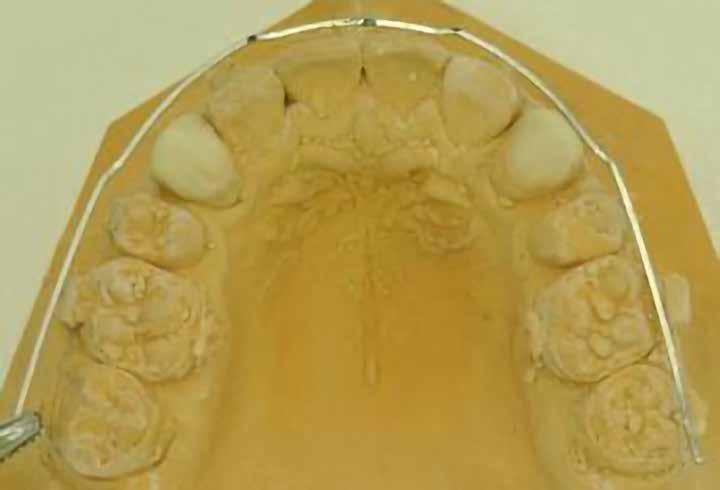

Dr. Ivana Dubovská, dr. Barbora Vágnerová, dr. Wanda Urbanová (Csehország), Dr. Veiszenbacher Éva, dr. Borbély Zoltán, dr. Borbély Péter (Dr. Borbély Fogszabályozási Stúdió, Budapest)

SZEMFOG ÉS KISŐRLŐ FORMÁZÁSA KISMETSZŐ APLÁZIA RÉSZÁRÁSSAL

TÖRTÉNŐ KEZELÉSE SORÁN

Absztrakt

A hiányzó oldalsó kismetszők részárással történő kezelése során a szemfogak és oldalsó fogak meziális mozgatása közben a fogszabályozó orvosnak csiszolással kell a fogak formáját igazítani. Már a kezelés elejétől a szemfog elcsiszolása nem csak az incizális részre kell hogy kiterjedjen, hanem az approximális, palatinális és a vesztibuláris felszín éli negyedére is. Így érhetünk el egy rövidebb klinikai koronát, a vesztibulo-orális méret csökkenését, egy incizális élet, valamint a szemfog megfelelő pozicionálását a kismetsző helyén. A túl széles szemfog megakadályozza a megfelelő interkuszpidáció kialakítását az oldalzónában. A palatinális felszín elcsiszolásával biztosítjuk az interferenciák nélküli metszővezetést, és a megfelelő overjetet a frontfogak enyhe érintkezésével. Ha a szemfogra a későbbiekben esztétikai pótlás készül, a megfelelő approximális elcsiszolás (az esztétikai fogorvossal történő egyeztetés után) biztosítja a zenith kívánatos pozícióját a későbbi felépítéshez. A mezializált kisőrlő palatinális csücskének elcsiszolására csak akkor van szükség, ha ez akadályozza a megfelelő fogérintkezést. Az első kisőrlő mindkét csücske fontos a már a szemfog helyén álló fog esztétikai és funkcionális beállításához.

A szemfog oldalsó kismetsző helyére történő bemozgatása során a fog átalakítása javasolt a két fog eltérő morfológiai adottságai miatt (1. a-b. ábra). A fog kontúrozása, vagy úgynevezett formázása magába foglalja az approximális felszínek elcsiszolását, valamint a többi fogfelszín igazítását a kívánt fogformának megfelelően [1].